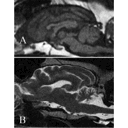

IRM CN cerv.png

UCDavis dog MRI.jpg